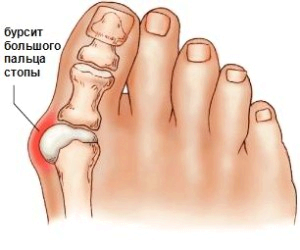

Але з віком відбуваються певні зміни, що впливають на вигляд ноги, викликаючи цим дискомфорт. У деяких жінок з віком близько великого пальця утворюється шишка - так починається бурсит стопи.

Така освіта називається бурсит великого пальця. Поразка суглоба в даній області відбувається поступово. При запущеній стадії хвороби ця шишка костеніє, виникають болі через запального процесу, що відбувається всередині. В результаті людині складно підібрати взуття, в якій було б зручно ходити.

Бурсит великого пальця стопи викликає деформацію суглоба. Відбувається нахил пальця, і утворюється пухлина. На нозі це виглядає як випинання кісточки біля великого пальця. Іноді суглоб деформується настільки, що відбувається зсув. При цьому сусідній палець випинається наверх.

Запалення великого пальця стопи починається з невеликого м'якого освіти в цій галузі. Змінюється естетичний вигляд ноги. Згодом шкіра червоніє і виникають болі. Відсутність своєчасного лікування дозволяє хворобі прогресувати далі.

Відбувається деформація великого пальця, і він викривляється. Згодом утворюється тверда шишка, або кісточка, як її називають в народі. Утворюється так звана кісткова мозоль. Шкірні покриви знаходяться в стані хронічного роздратування. Виникають постійні болі, що заважають пересуванню. Деформуються інші пальці.